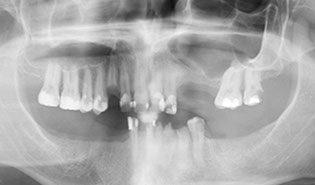

i) Damaged, broken and missing teeth

ii) Treatment Planning, including 3d cone beam scans